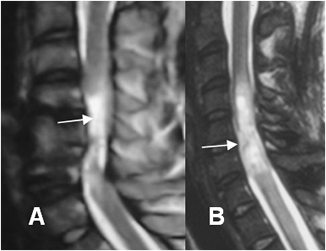

Fig 181. Sección medular.

A y B: RM sagital en T2. Solución de continuidad en el cordón medular por sección y retracción de los extremos.